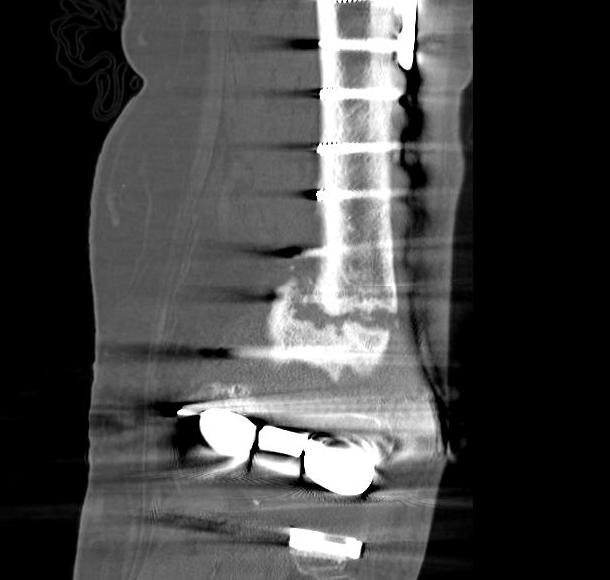

4.  Revision TKR

Indications

- very distal fracture

- insufficient bone stock

- loose prosthesis

Components

- stemmed, constrained implant

- tumour prosthesis

TKR Periprosthetic Fracture APTKR Periprosthetic Fracture LateralTKR Periprosthetic Fracture Revision APTKR Periprosthetic Fracture Revision Lateral